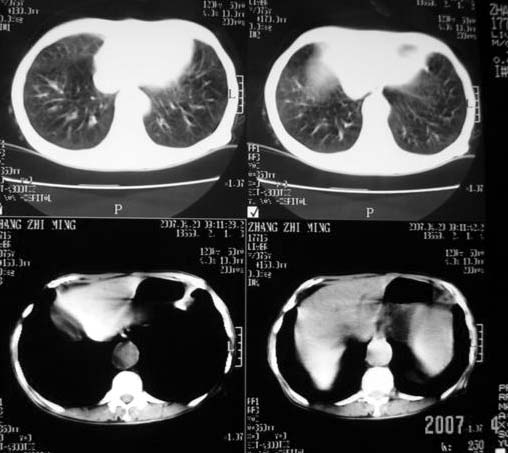

以下是引用dyqct在2007-4-20 16:38:00的发言:[br]考虑:1、巨脾;[br] 2、肝内多发低密度,首先考虑转移瘤;[br] 3、胆囊多发结石。

以下是引用andymaomao在2007-4-20 16:47:00的发言:[br]肝脾增大,肝内胆管扩张,且可见多发小囊性低密度灶,胆囊窝区高密度影,手术化疗病史,贫血....[br]1.肝脾大及贫血与术后化、药疗有关;[br]2.胆囊窝区高密度影,术后改变?肝内胆管扩张,积液?[br]3.肝内多发低密度灶,性质?建交增强